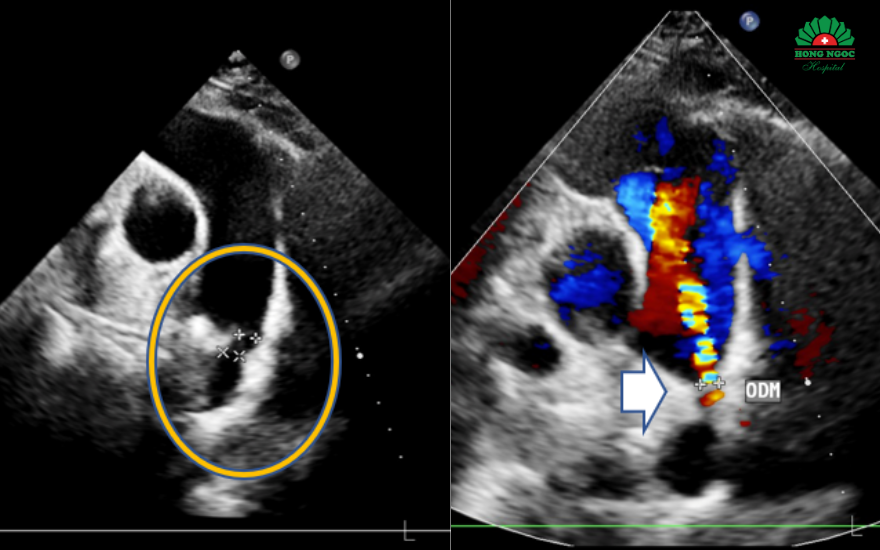

동맥관 개존증이 확인된 초음파 영상

즉시 시행된 심장 초음파 검사 결과, N.T.N 씨는 '동맥관 개존증'을 앓고 있는 것으로 확인되었습니다. 동맥관 개존증은 태아 시기에 대동맥과 폐동맥을 연결하던 혈관 통로가 출생 후에도 닫히지 않고 남아 있는 선천성 심장 기형입니다. 신생아에게는 흔하지만, 성인에게서 발견되는 경우는 매우 드물고 폐 고혈압, 심부전 등 심각한 합병증을 유발할 수 있습니다.

1시간도 채 되지 않아, 홍옥 종합병원 심장 중재 시술팀은 환자의 동맥관을 완전히 폐쇄하는 데 성공했습니다. 시술 후 초음파 영상에서는 비정상적인 혈류 흐름이 사라졌고, 장치는 안정적으로 고정된 것이 확인되었습니다. N.T.N 씨는 증상이 빠르게 호전되어 단 2일 만에 건강하게 퇴원할 수 있었습니다.